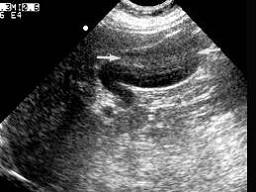

患者女,20岁,健康体检如图,根据胆囊声像图,提示?(?)A.胆囊癌B.胆泥C.胆囊泥沙样结石D.混响伪像E.以上都不是

问题 患者女,20岁,健康体检如图,根据胆囊声像图,提示?(?)

选项 A.胆囊癌 B.胆泥 C.胆囊泥沙样结石 D.混响伪像 E.以上都不是

答案 D